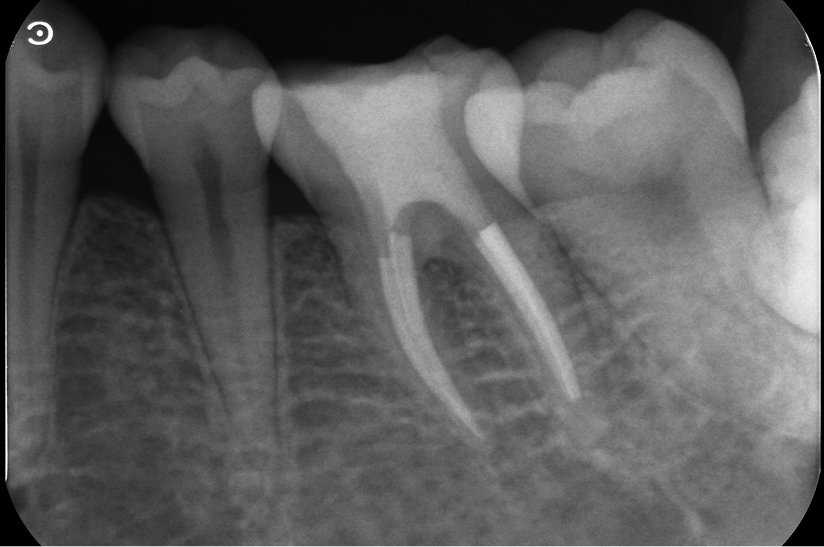

長期予後を見越した根管治療の症例

タップで写真の拡大ができます。

Before

After

主訴

症状はないが、治療が必要な箇所があればしっかり治療しておきたい。

治療内容

イニシャルトリートメント(根管治療・大臼歯)、ファイバーポストコア、セラミッククラウン

治療期間

3ヶ月

治療費用

352,000

治療の

リスク

根尖部透過像が完全に消失しない可能性があります。